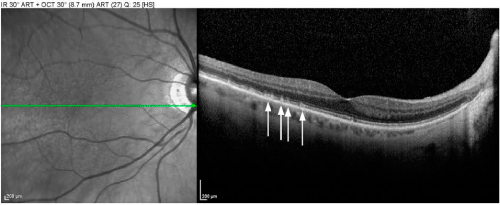

| Figure 4: Pseudo-drusen are best distinguished from standard drusen via optical coherence tomography. Whereas cuticular drusen and soft drusen appear as round punctate accumulations under the retinal pigment epithelium (RPE), pseudo-drusen (or subretinal drusenoid deposits) are interconnected accumulations above the RPE. |